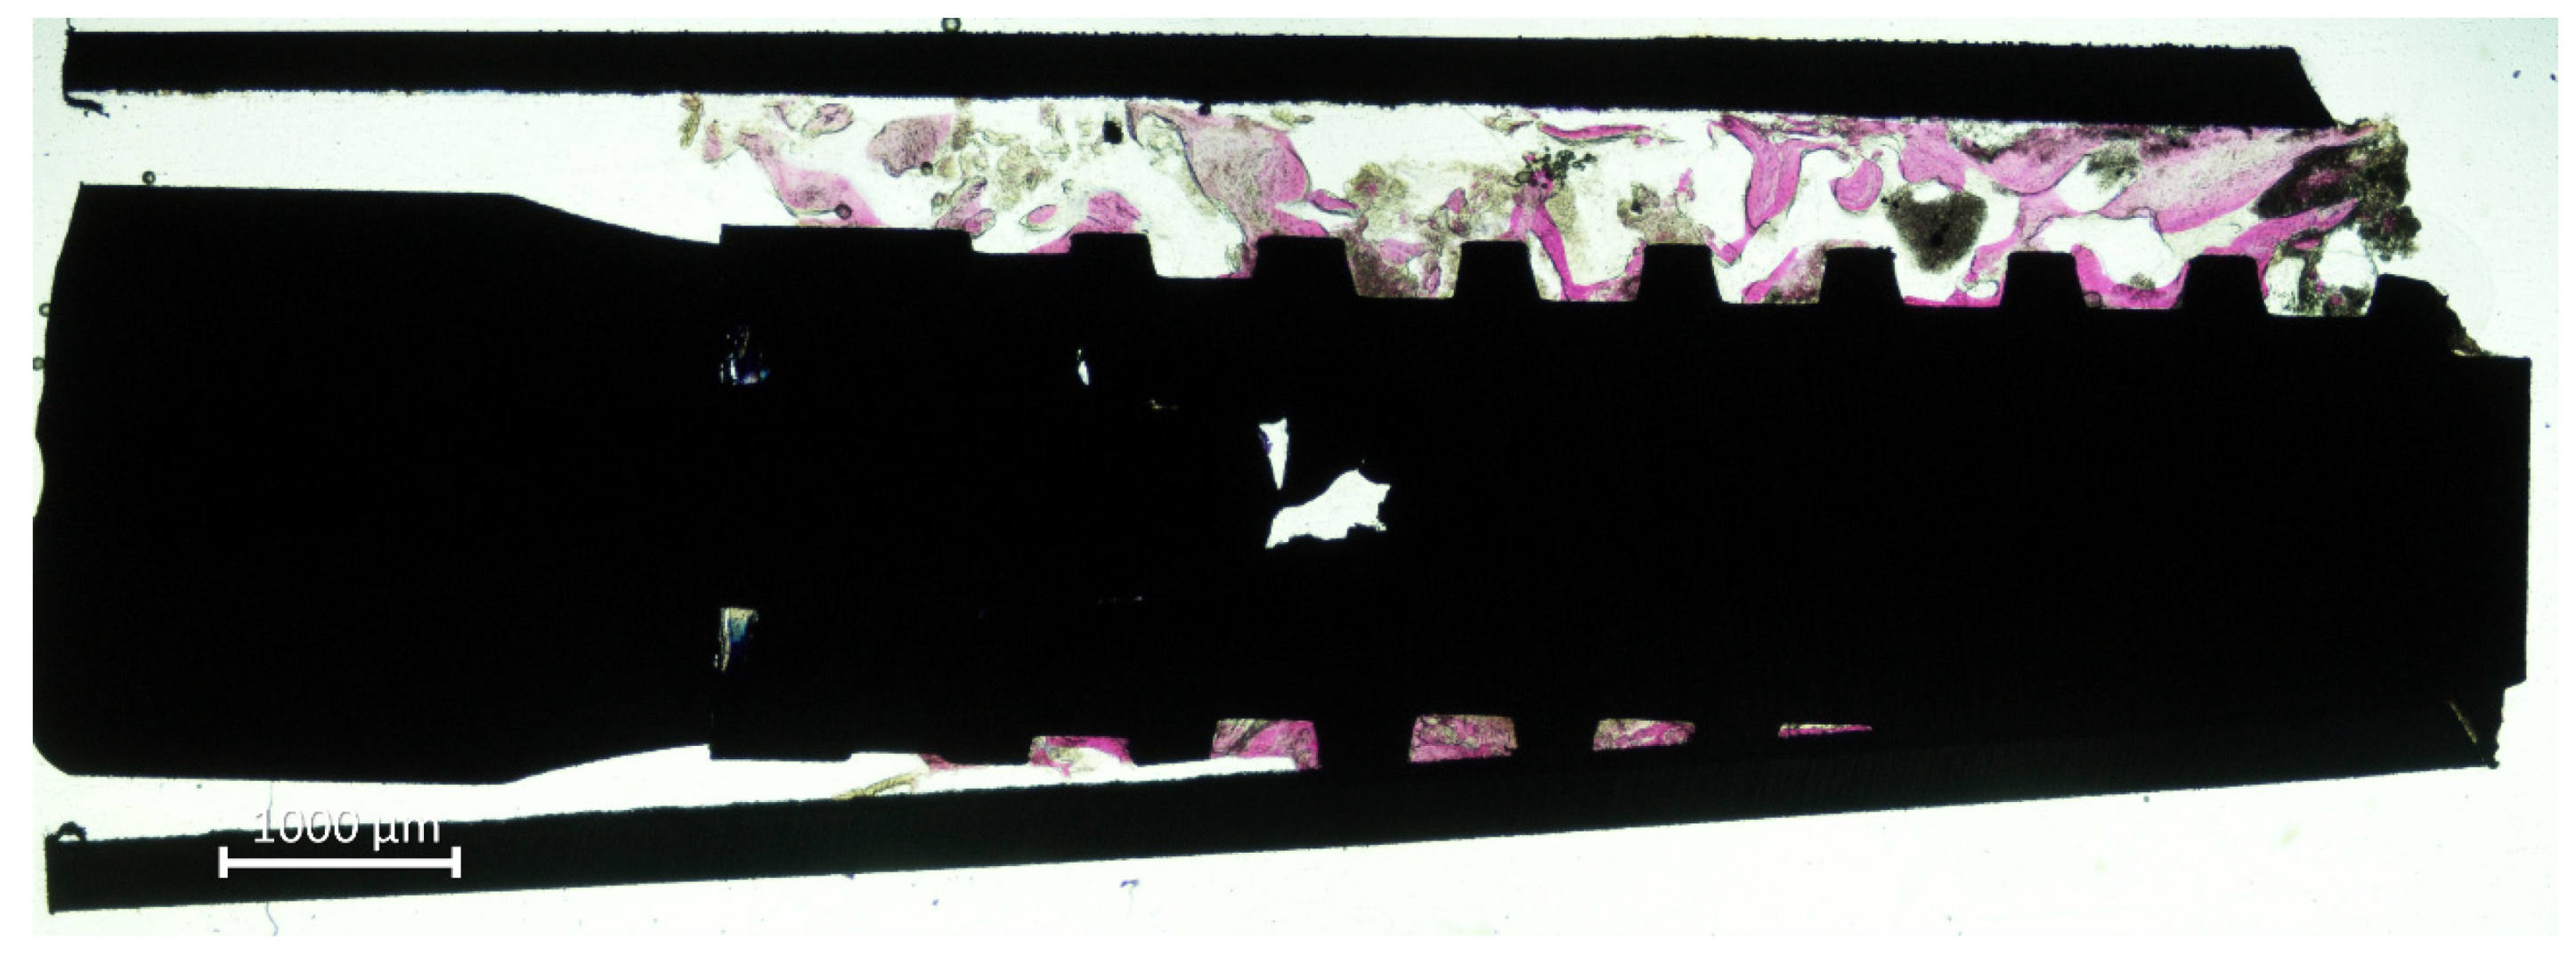

All biopsies were retrieved applying the eccentric method (Figure 3).

Figure 3.

Retrieved biopsy. Note the eccentric position on the mini-implant within the trephine.

The mini-implants presented new bone around and in contact to the surface (Figure 4a) while, in other regions, large amounts of biomaterial were still present (Figure 4b).

Figure 4.

(a), New bone anchored to the implant surface. (b) Large amounts of biomaterial were still present.

In several instances, the biomaterial was found overlaying the new bone, taking on a foggy appearance (Figure 5a–d). In such cases, that new bone was assuming a different feature compared to new bone outside the biomaterials, as if the two tissues were interpenetrating each other (interpenetrating bone network; IBN).

Figure 5.

(a–d) Images showing new bone formed around and within the graft residues (interpenetrating bone network; IBN).